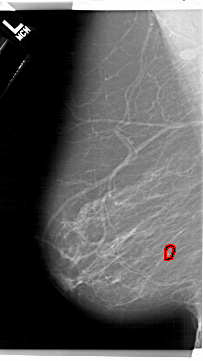

A_1192_1.LEFT_CC

LEFT_CC LINES 6871 PIXELS_PER_LINE 3661 BITS_PER_PIXEL 12 RESOLUTION 43.5 OVERLAY

FILE: A_1192_1.LEFT_CC.OVERLAY

TOTAL_ABNORMALITIES 1

ABNORMALITY 1

LESION_TYPE CALCIFICATION TYPE FINE_LINEAR_BRANCHING DISTRIBUTION LINEAR

ASSESSMENT 4

SUBTLETY 2

PATHOLOGY MALIGNANT

TOTAL_OUTLINES 1

BOUNDARY